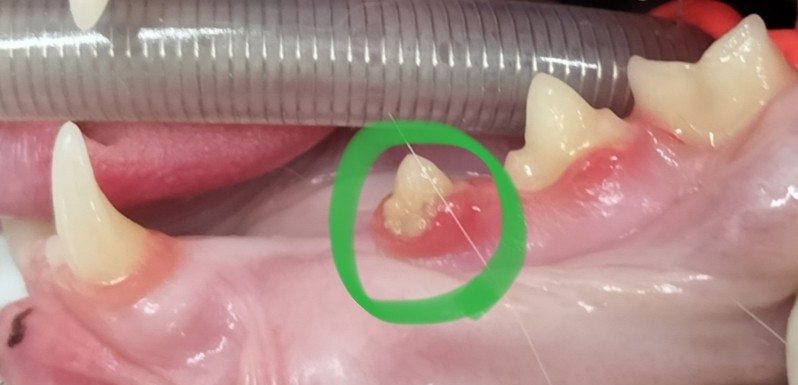

🩻実際の吸収病巣の症例

【写真:実際に抜歯した歯の写真】

このように、肉眼では「歯が少し赤いだけ」と見えることもありますが、実際には歯の内部が完全に崩壊しているケースもあります。